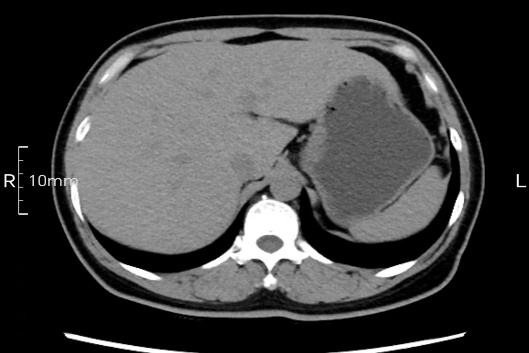

看看下面三幅便知遵醫(yī)囑的重要性。

沒禁食,胃內(nèi)全是食物,導(dǎo)致胃壁顯示不清。